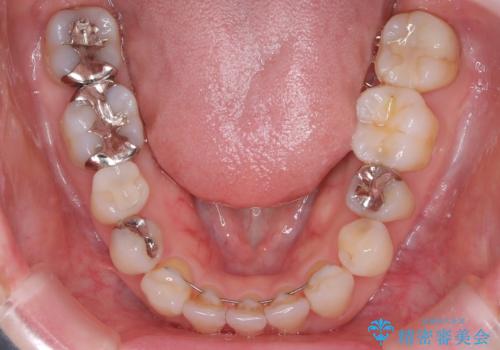

左上4近心に実質欠損を認め、遠心から咬合面にかけてはCR修復が施されていたため、MODインレー窩洞としました。

インレー接着操作時はラバーダム防湿を行っています。